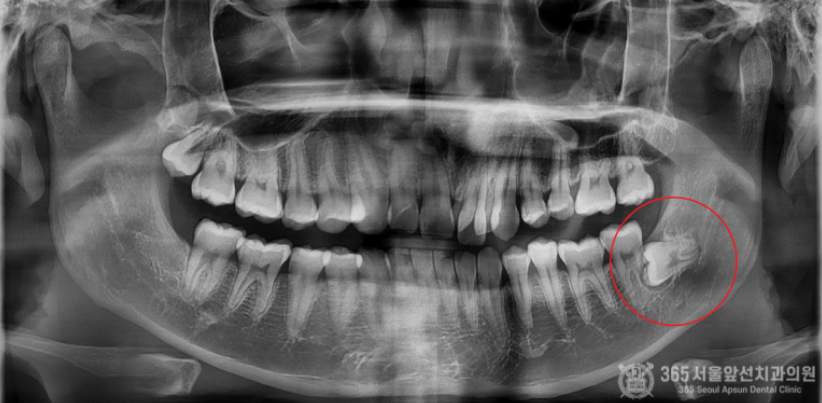

아래턱에 매복사랑니가 있는데, 집근처 동네치과에서 발치가 불가능하다고 대학병원에 가보라고 했어요. 오늘은 완전수평 매복 사랑니의 발치 증례를 소개해드리겠습니다. 집 근처 치과에 방문했다가 완전수평 매복사랑니 발치가 불가능하다는 판정을 받은 환자분께서 내원하셨습니다. 촬영일시 : 2024.05.15. 초진 엑스레이 사진입니다. 완전히 수평으로 매복되어 있으며, 신경관과 뿌리가 겹쳐져 있는 양상이 관찰됩니다. 환자분께선 발치가 불가능할까봐 걱정이 많으셨으나 걱정하지말라고 안심시켜드리고 매복 사랑니 발치를 진행했습니다 ㅎㅎ 촬영일시 : 2024.05.15. 3차원 CT 영상입니다. 뼈 속에 완전히 파묻힌 사랑니를 볼 수 있습니다. 촬영일시 : 2024.05.15. 신경관과 뿌리가 겹쳐져 있는 양상도 관찰됩니다. 조심스럽고 안전한 발치가 필수적이겠습니다. 촬영일시 : 2024.05.15. 발치 후 엑스레이 사진입니다. 발치에 소요된 시간은 총 10분으로 정확하고 빠르게 발치해드렸습니다. 빠르고 정확한 진료를 추구하는 강동우 대표원장이었습니다. 365서울앞선치과의원은 365일 늘 가까운 서울대학교 치과병원을 지향합니다! [ 치료기간: 2024년 5월15일 ] ※ 365서울앞선치과의원의 모든 포스팅은 각 진료과 의료진이 직접 작성합니다. 365서울앞선치과의원 블로그의 임상 케이스 게시물은 환자분께 의학적으로 정확하고 상세한 정보를 드리기 위해 각 진료과 의료진이 직접 작성하며, 모든 증례 사진은 본원 의료진이 직접 시술한 증례를 촬영한 것으로, 의료법 제23조, 제56조에 의거하며 환자분의 동의를 얻어 포스팅에 사용하였습니다. 또한 해당 케이스는 본 환자분의 치료 결과이며, 환자 상태에 따라 치료의 결과는 달라질 수 있습니다. |